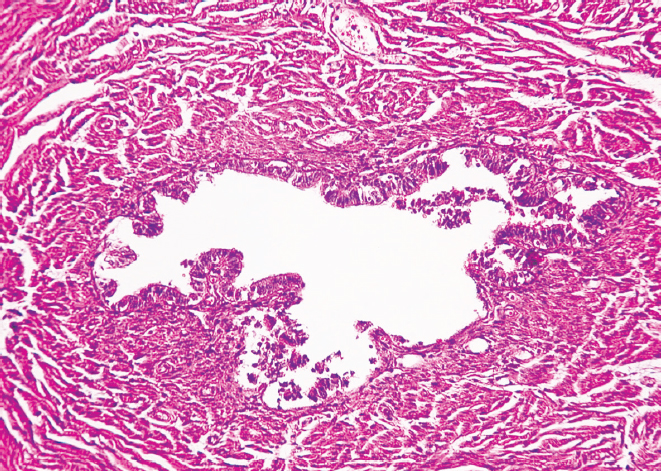

Перешеек и воронка маточных труб женщин старческого возраста характеризуются наличием утолщенных складок слизистой оболочки и уплощенным эпителием. Наблюдается неравномерное сужение просвета как в перешейке, так и в воронке, обусловленное близким друг к другу расположением складок слизистой оболочки, частично объединенных между собой. В старческом возрасте циркулярный и продольный слои мышечной оболочки выглядят истонченными в сравнении с образцами, взятыми для исследования у женщин молодого возраста. Наряду с этим у женщин старческого возраста выявлено разрастание соединительной ткани в стенке маточной трубы как в области воронки, так и в области перешейка. Видны скопления адипоцитов, локализующихся в подсерозной основе, где сосуды в утолщенной стенке располагаются группами (рис. 3, 4).

Рис. 3. Фрагмент перешейка маточной трубы женщины в возрасте 86 лет. Окраска гематоксилином и эозином, увел. ×10

Рис. 4. Фрагмент воронки маточной трубы женщины в возрасте 86 лет. Окраска гематоксилином и эозином, увел. ×10